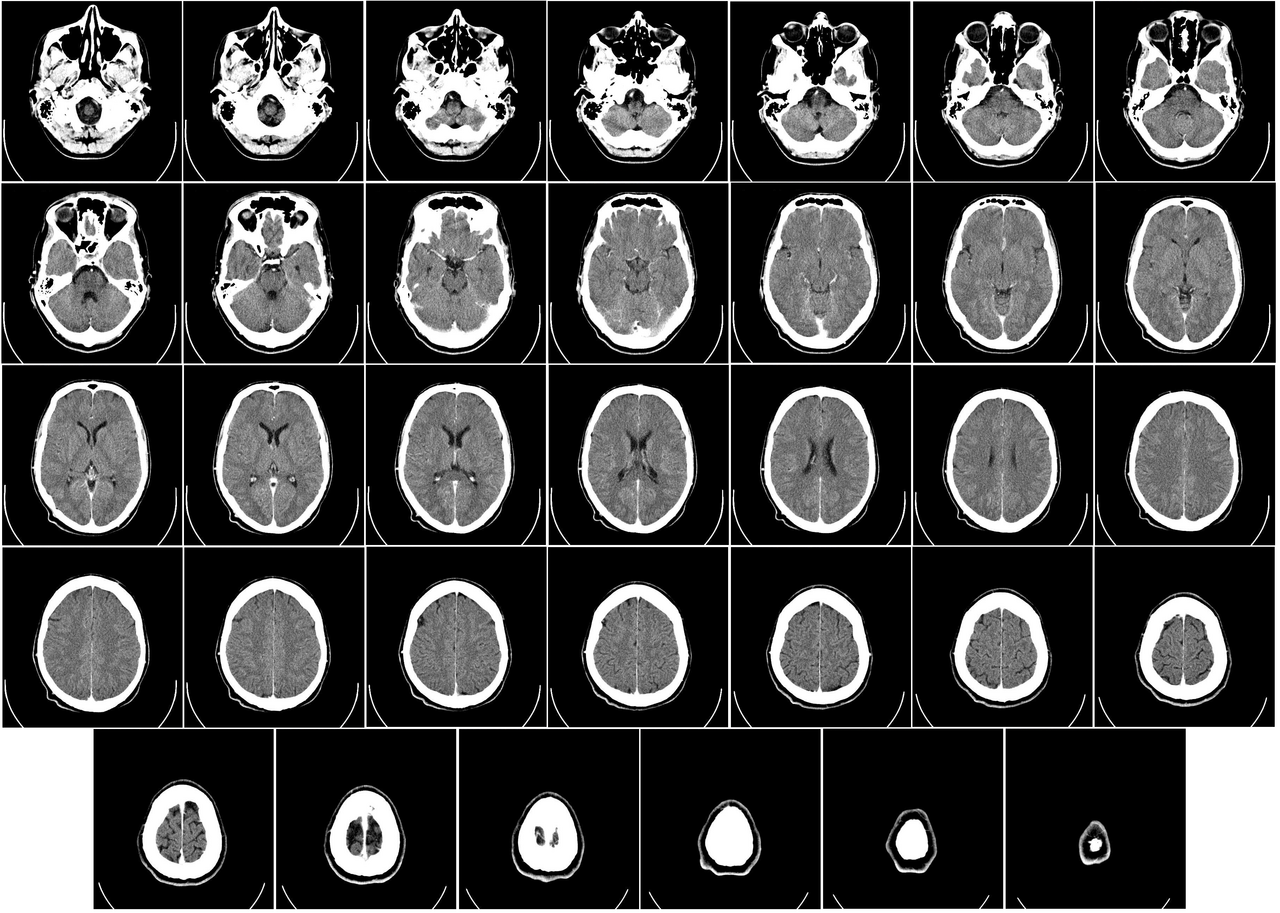

Dr. Gottfried Schlaug sat in a University of Heidelberg laboratory in 2004, staring at scans that fundamentally altered our understanding of the human skull. These images revealed more than abstract emotion or fleeting thought.

They displayed dense, physical matter that looked starkly different from the brains of people who never touched a massive orchestral percussion kit or a Stradivari and a bow. The scans showed that musicians possessed larger volumes of gray matter in the left auditory cortex and the posterior intural parietal sulcus. This density occurs because the brain adapts to the relentless, heavy demands of auditory processing. The brain performs a literal, physical reconfiguration of its biological hardware.